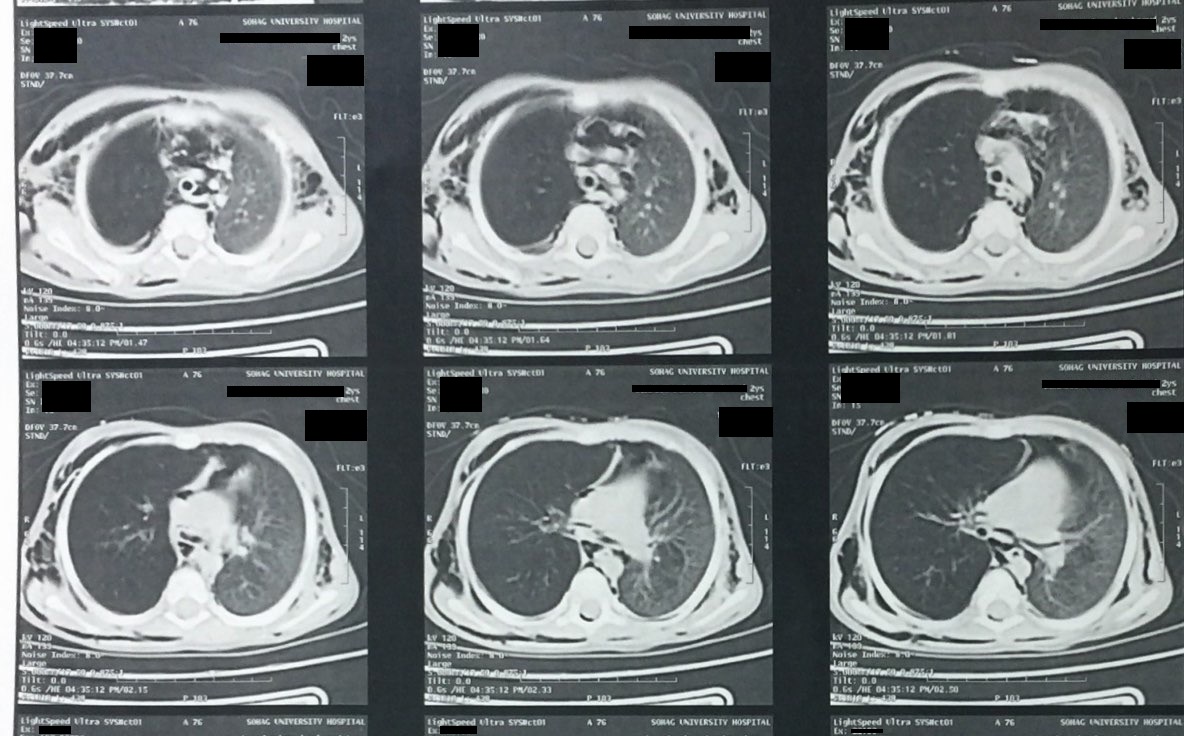

Pulmonary actinomycosis presenting as postobstructive pneumonia

From www.ijidonline.com

Pulmonary actinomycosis presenting as postobstructive pneumonia What Does Decreased Air Entry Mean Web using a stethoscope, the health care provider may hear normal breathing sounds, decreased or absent breath sounds, and. Web reduced intensity (decreased air entry) muffled breath sounds as a result of pleural effusion, pneumonia, chronic obstructive. Swelling, blockages or mucus in your. Web abnormal breath sounds may indicate a respiratory illness, heart disease, infection, or other problems. Web air. What Does Decreased Air Entry Mean.